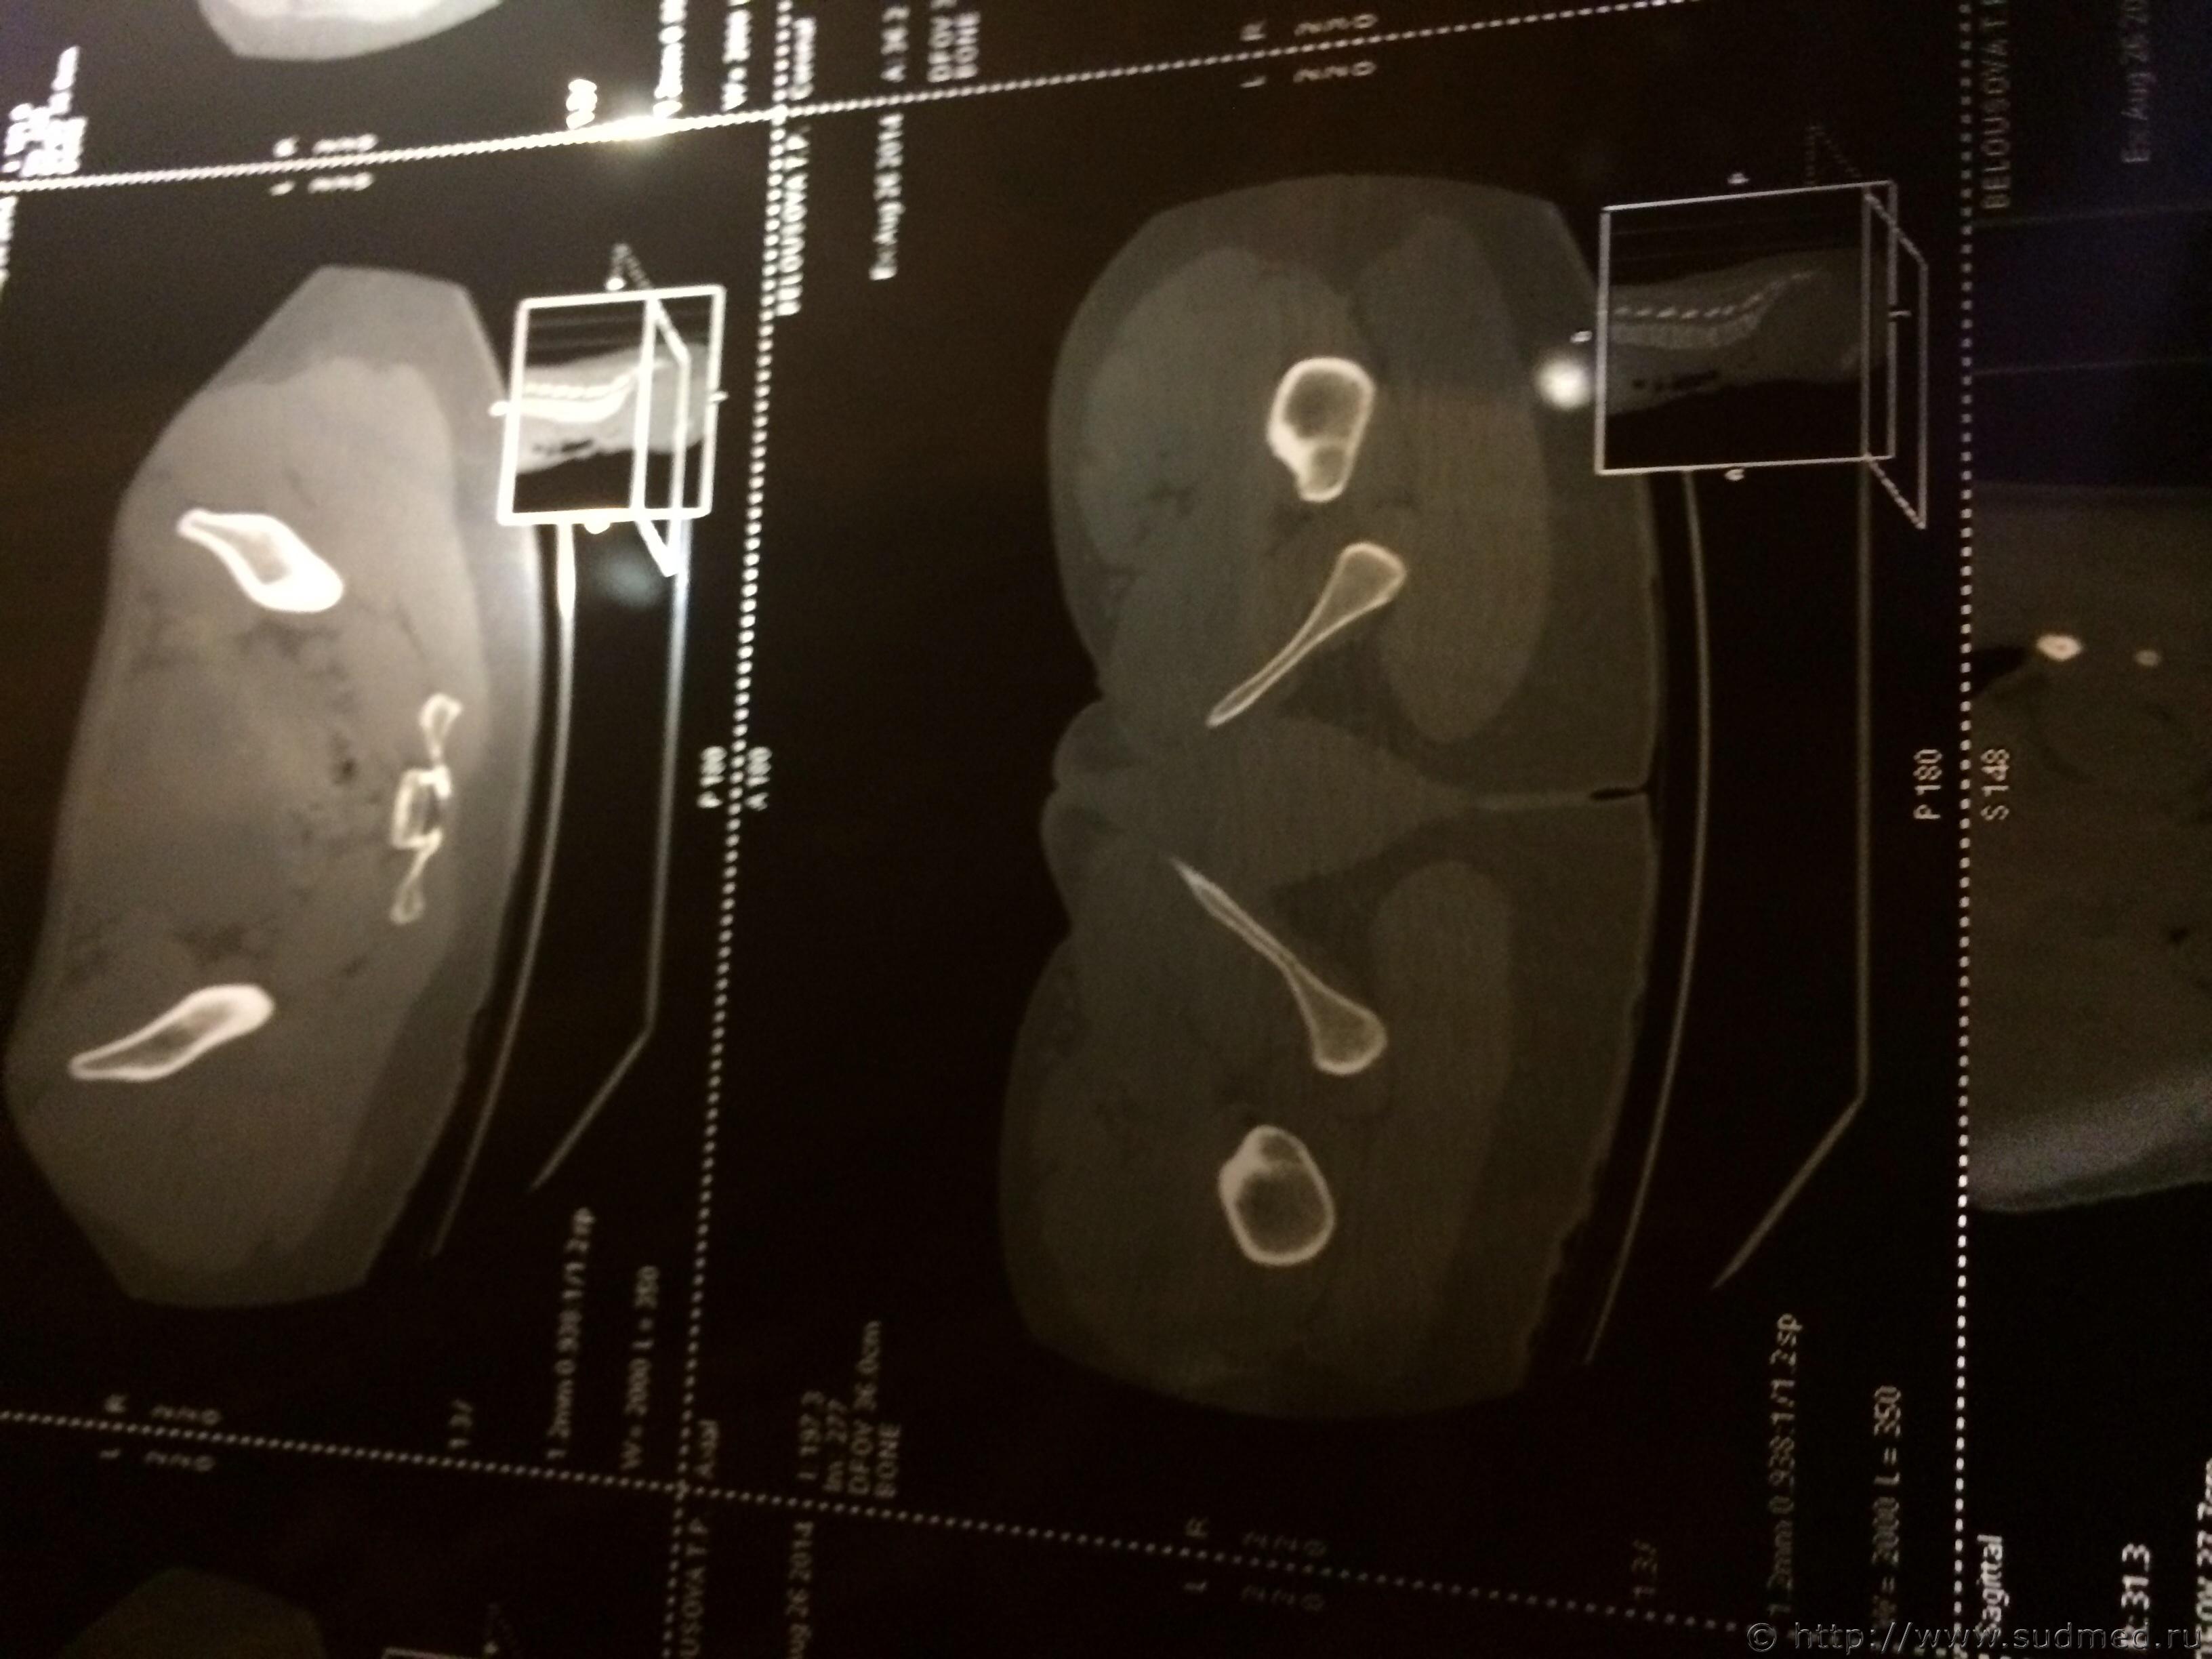

Спасибо! У меня результаты КТ, ошиблась)

КТ

Как мне видится - вертикальный перелом крестца. Тяжкий вред.

Впрочем, оставляю небольшую вероятность, что я не видел все сканы, да и качество их здесь, разумеется, хуже, чем изображение на пленке или на экране компьютера у врача, работающего на томографе.